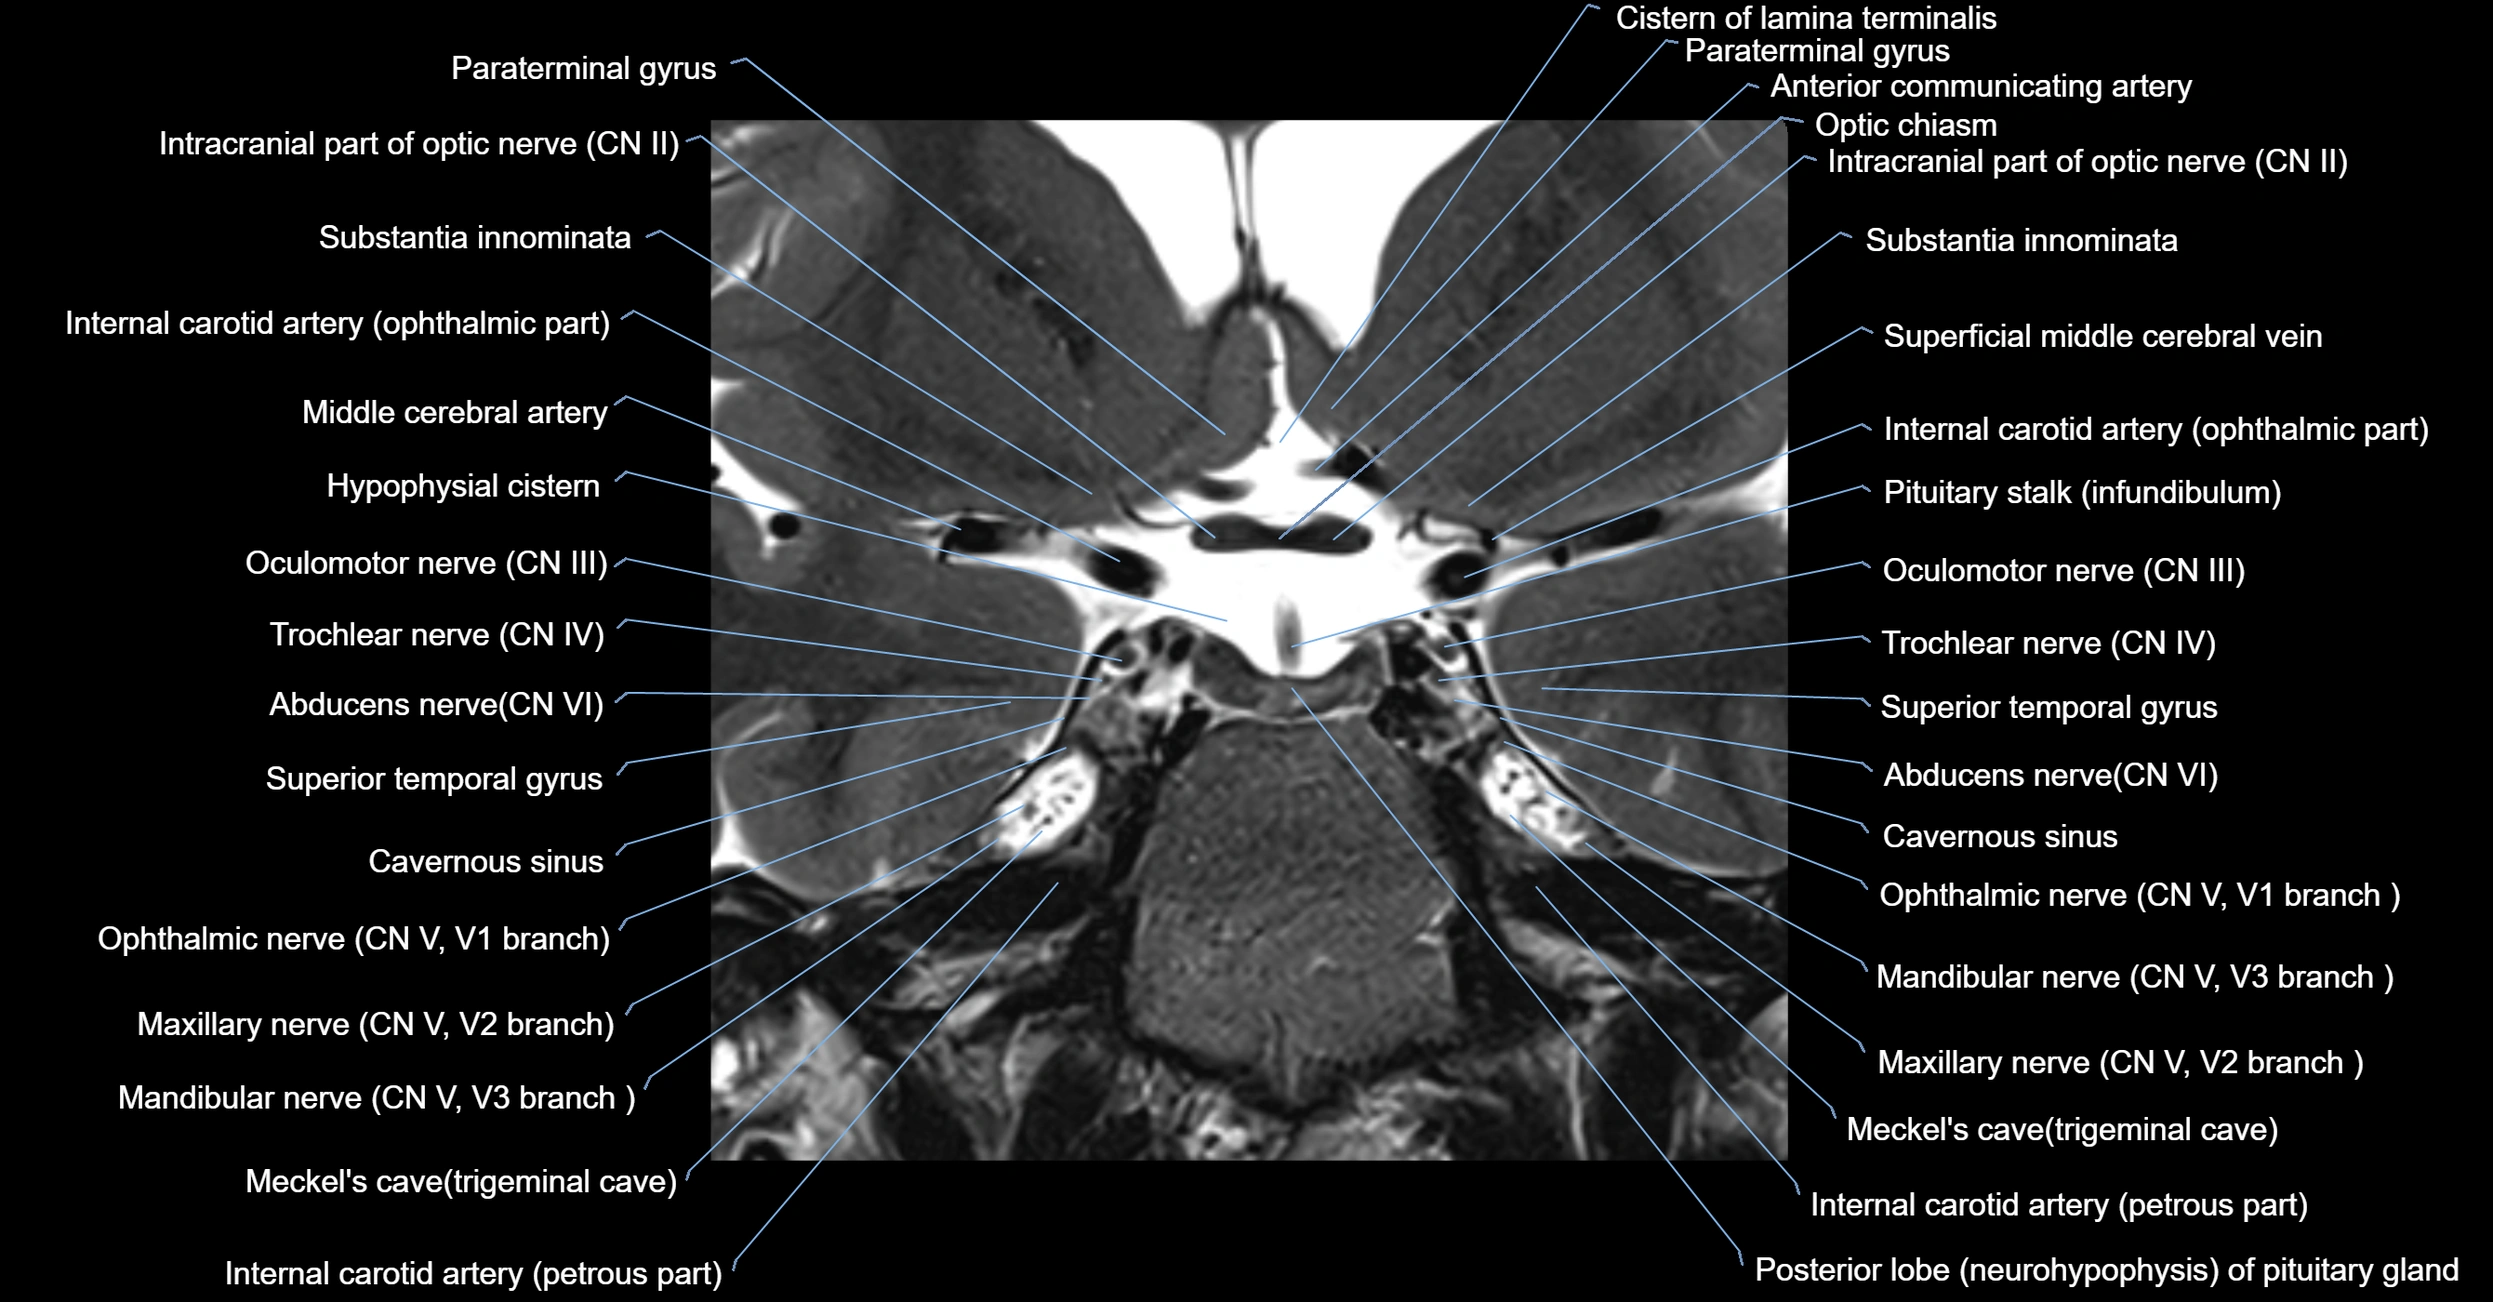

MRI Appearance

-

The abducens nerve is a small, thin, linear structure

Best visualized on high-resolution T2-weighted 3D MRI sequences (e.g., FIESTA or CISS)

Seen as a hypointense (dark) line running from the brainstem at the pontomedullary junction, traversing the prepontine cistern, and entering Dorello’s canal under the petrosphenoidal ligament, then into the cavernous sinus, and finally the orbit

May be challenging to visualize in standard MRI due to its small size

Pathology may be inferred by absence, displacement, or enhancement of the nerve

MRI images